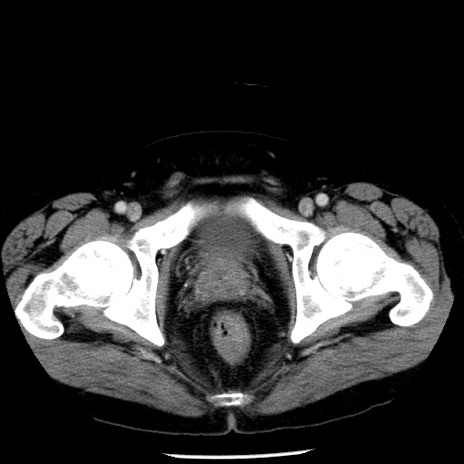

症例29(横断像)

【症例】40歳代男性

【現病歴】2日前から胃痛あり。徐々に周期的な激痛に変化した。本日になっても激痛があるため受診。

【身体所見】意識清明、BT 38-39℃台あり、腹部:膨満、やや硬、右下腹部に圧痛あり。

【データ】WBC 8500、CRP 23.26